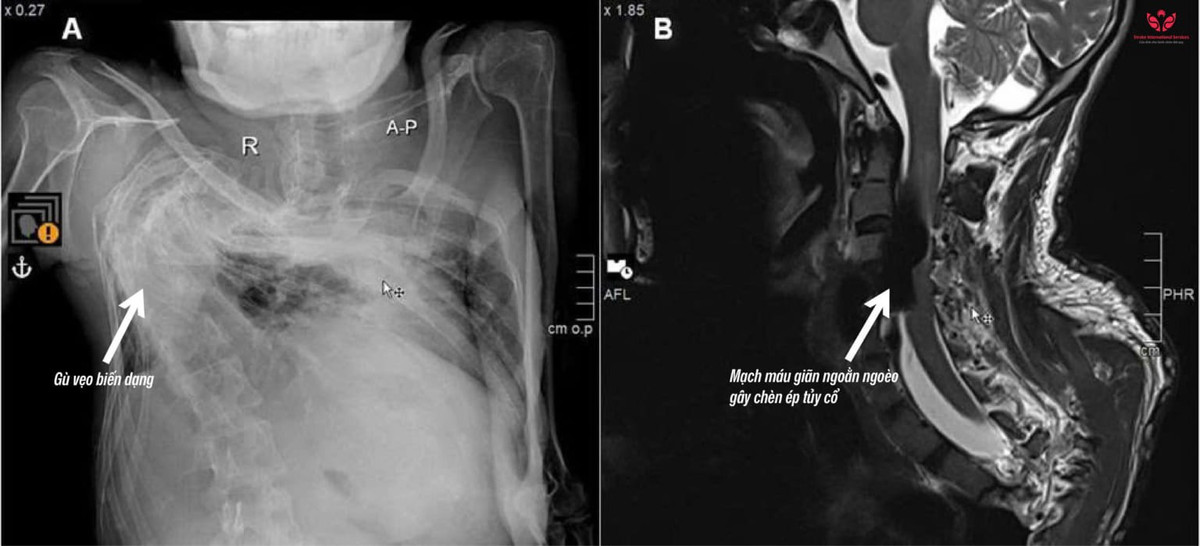

Qua thăm khám và chụp MRI, bác sĩ phát hiện anh N. bị bệnh rò động tĩnh mạch vùng cột sống làm cho tĩnh mạch quanh tủy sống vùng cổ giãn ngoằn ngoèo, tạo thành một khối lớn gây chèn ép. Tình trạng này là nguyên nhân khiến anh N. bị yếu liệt tay chân, đau nhức và khó vận động. Bác sĩ nhận định, đây là một bệnh lý cực kỳ hiếm gặp.

Trường hợp hiếm gặp: Rò động tĩnh mạch cột sống trên nền gù vẹo nặng - Ảnh BVCC

Theo BS.CKI Trần Nguyễn Khánh – Đơn vị Can thiệp mạch DSA, Bệnh viện S.I.S Cần Thơ: Trường hợp này phức tạp hơn nhiều so với thông thường vì cột sống biến dạng nặng, giải phẫu mạch máu bị thay đổi theo, khiến việc tiếp cận điều trị trở nên rất khó khăn.